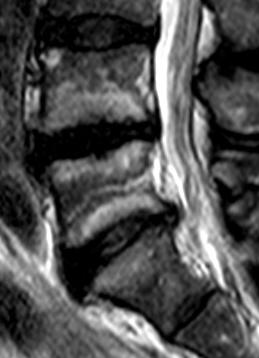

Discopathie MODIC 1 évoluant en MODIC 2. Notez le respect des corticales et l'absence de prise de contraste discale, malgré le franc hypersignal T2 du disque. Evolution à 1.5 ans en discopathie MODIC 2